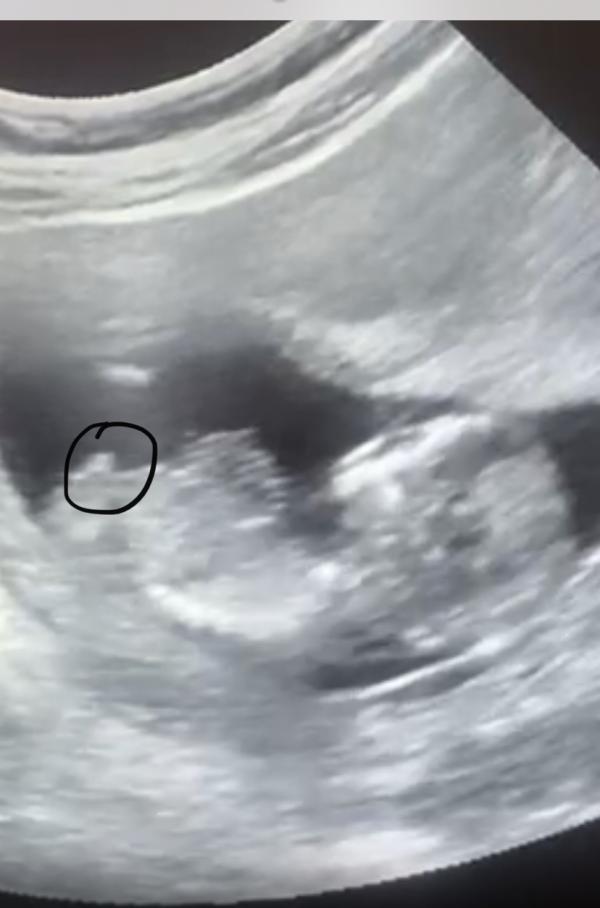

1 скрининг

Девочки как думаете пацан ?)

Да, тут бугорки как раз по которым можно определить, но на вашем фото, к сожалению, не он))

У моей дочки был в 10 недель девочкин бугорок. Узистка говорит-на мальчика больше похоже, а я смотрела и смотрела на угол и думала - ну какой тут мальчик, девочка же. Но бугорок чётко был виден и угол хороший, а у вас же ребёнок на фото лежит во всю длину - с головы до ног, вид сбоку, конечно тут никаких бугорков не будет видно.

Это ноги, похоже на палец.)) Пола на этой фотке не видать.

Если это бугорок, то пацан, потому что вверх смотрит, а так половые органы ещё не сформированы

Смотрят пол на таком сроке «снизу» если ребёнок повернётся ))

Мне почему то кажется что это пуповина, т.к половые органы в другую сторону смотрят 🙂🙈

Это не писька ))